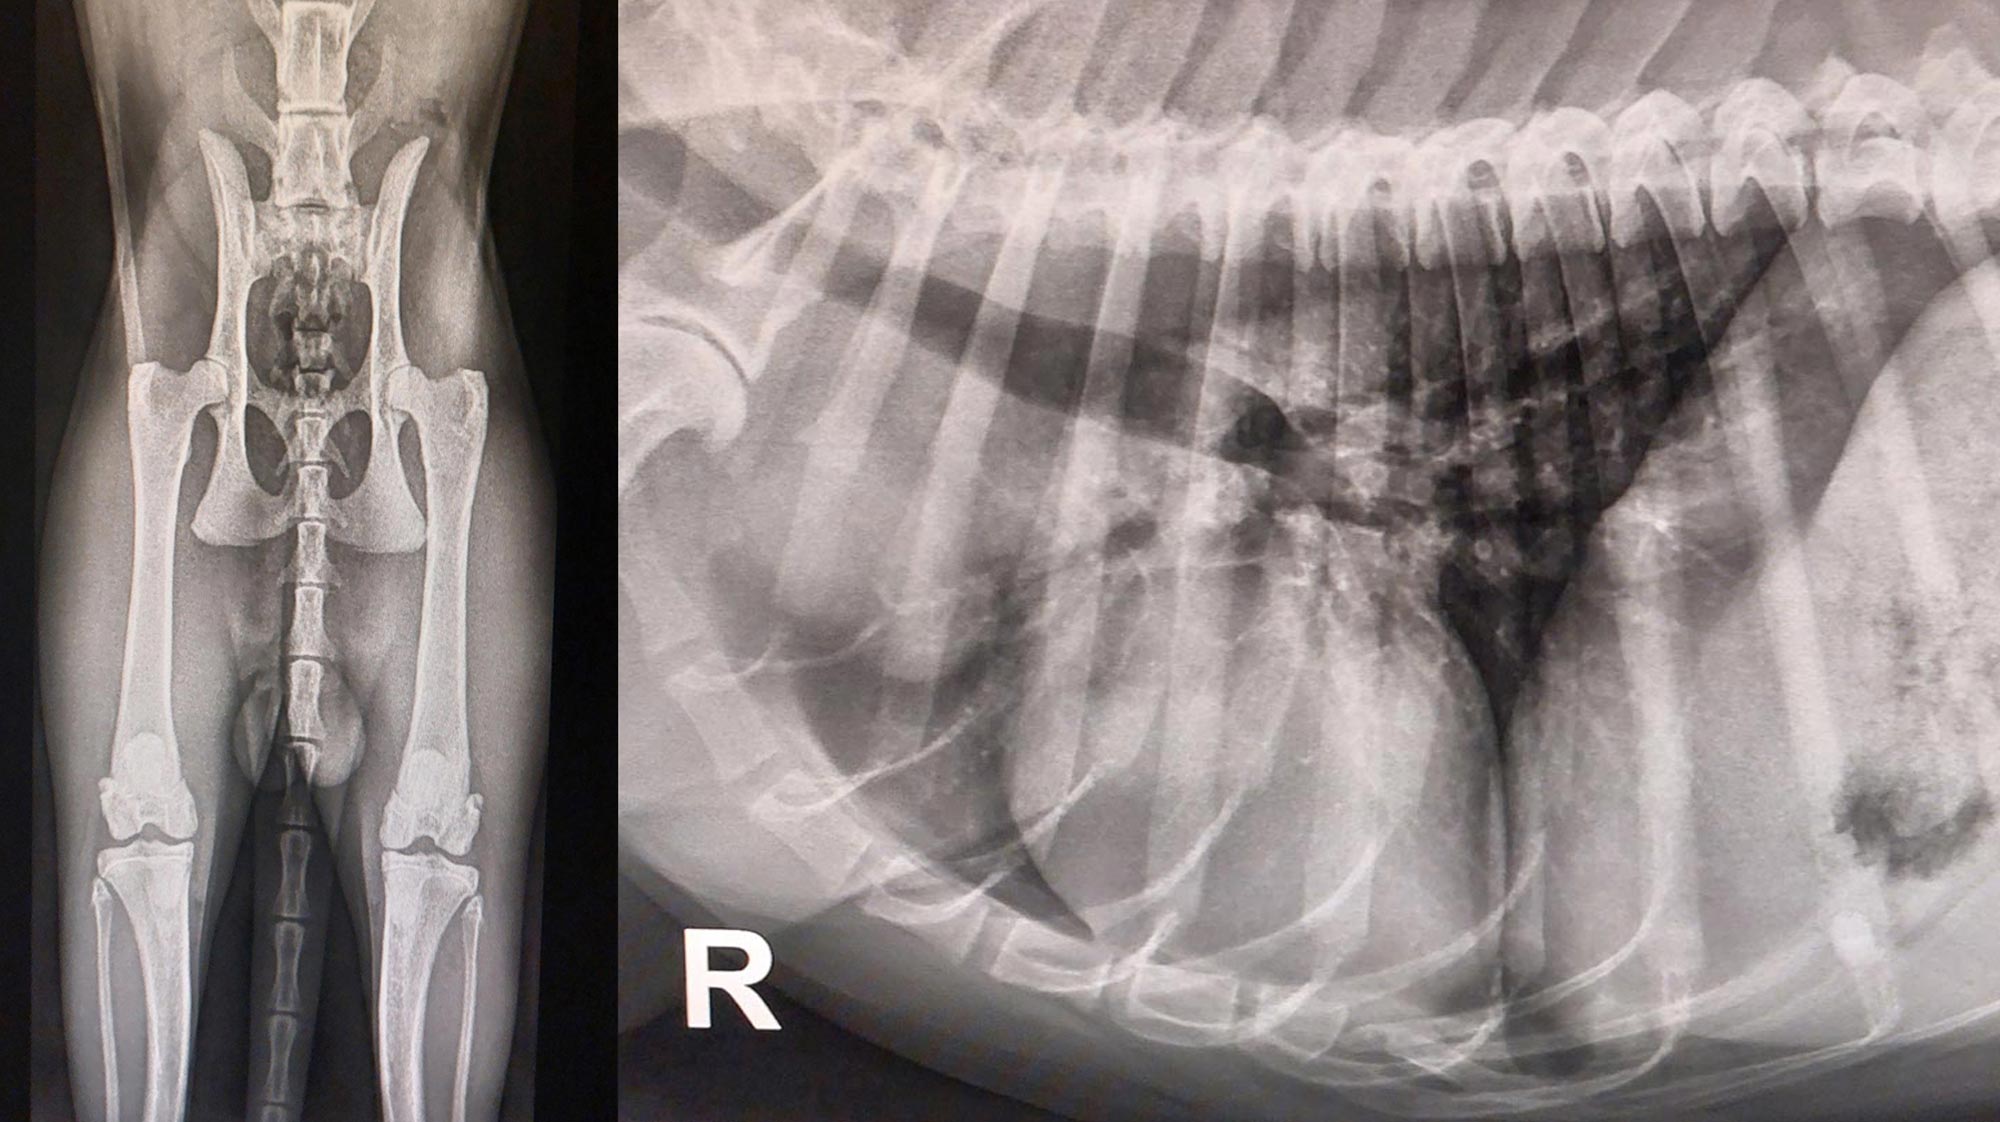

Digitales Röntgen

Wir verfügen über Digitales Röntgen, dem derzeit höchsten Niveau bei der Beurteilung von Knochenstrukturen. Durch die Digitalisierung ist zudem ein Versenden der Röntgenbilder per E-Mail an den Haustierarzt und an die Besitzer möglich.

Ein wichtiges Instrument in der Orthopädie ist das digitale Röntgen. Lahmheitsdiagnostik am wachen Patienten als auch Untersuchungen unter Ultrakurzzeitnarkose wird ergänzt durch unseren Bereich der Orthopädischen Chirurgie. So führen wir Operationen wie z. B. TTA (Tibial Tuberosity Advancement) bei Kreuzbandrissen, Toggle Pin bei Luxationen des Hüftgelenks, Bandersatz und Reparatur bei Rissen und Ruhigstellungen von Gelenken mittels externem Fixateur durch.